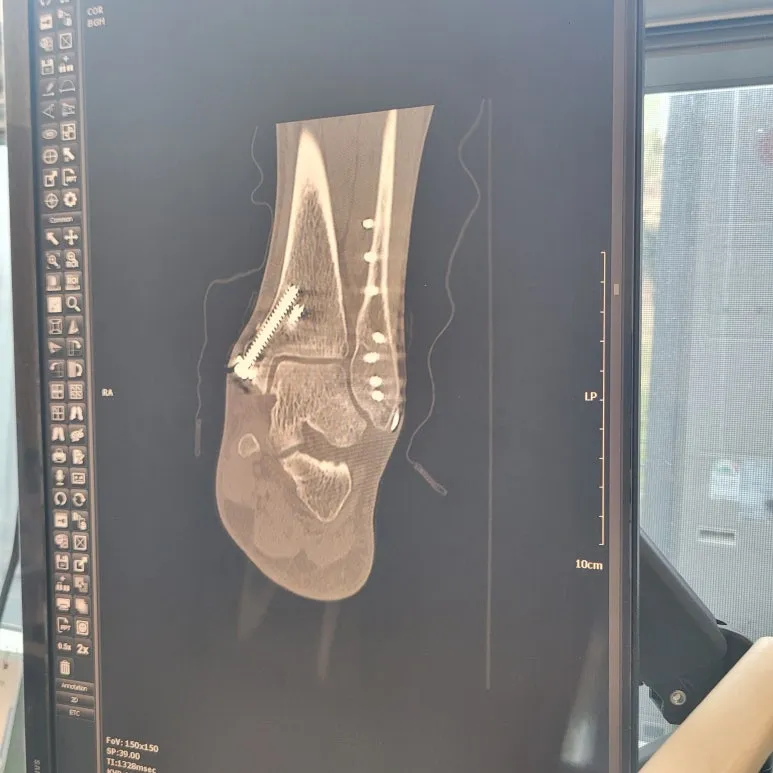

발목 철심 제거 수술!

2024년 5월 하산하다가 발목 골절이 생겼고 수술을 했고, 철심을 박았더랬죠. 1년 후 철심 제거 수술을 한다고 했지만 그건 눈에 들어오지도 않은 이야기였어요. 그 당시에는 세 군데 골절로 놀랐고, 휴일이라 바로 수술을 못했고, 부어서 못했고, 어느 병원에서 할 것인지 고민스러웠어요.